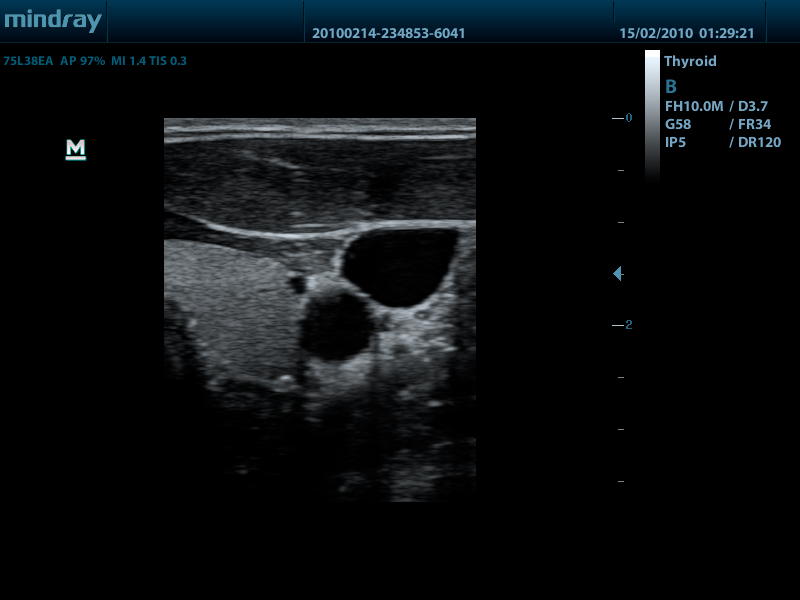

Линейный датчик 75L38EA (5.0/7.5/8.5/10.0/Н8.0/Н10.0 МГц, 38 мм)

Mindray DP-50 – портативная цифровая ультразвуковая система с ЖК монитором 15 дюймов (1024Х768)

- диапазон сканируемых частот от 2,0 до 14,0 МГц

Качество изображения:

- iBeam: функция улучшения разрешающей способности изображения

- iClear: функция подавления шумов на изображении для улучшения детализации и контрастности изображения